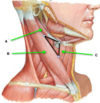

sternocleidomastoid muscle

platysma muscle

external jugular vein

anterior triangle:

mandible

sternocleidomastoid

anterior midline

anterior belly of digastric

posterior belly of digastric muscle

submadibular triangle:

anterior belly of digasric

posterior belly of digastric

mandible

muscular triangle:

superior belly of omohyoid muscle

sternocleidomastoid muscle

anterior midline

carotid triangle:

superior omohyoid belly

posterior digastric belly

sternocleidomastoid

submental triangle:

body of hyoid

anterior belly of digastric muscle on each side

sternohyoid muscle

submandiubular gland

omohyoid muscle:

superior belly

intermediate tendon

inferior belly

sternothyroid muscle

thyrohyoid muscle

carotid sheath:

common carotid artery

internal carotid artery

internal jugular vein

vagus nerve

internal carotid artery

external carotid artery

carotid sinus

internal jugular vein

vagus nerve

hypoglossal nerve

ansa cervicalis